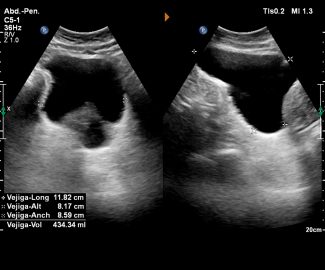

Especialista en diagnóstico por imágenes con más de 25 años de experiencia en el campo del ultrasonido y radiología digital. Trabajamos con equipos de alta tecnología garantizando la calidad y seguridad de nuestros diagnósticos, pues nuestra prioridad es la salud, bienestar y satisfacción de nuestros pacientes.

Sabemos que visitar un centro médico a veces genera nervios. Por eso, hemos creado un ambiente cálido, moderno y 100% seguro para ti. Desde nuestra cómoda sala de espera hasta nuestras áreas de ecografía, mamografía y rayos X, cada rincón está equipado con tecnología de última generación y diseñado para que te sientas en confianza.